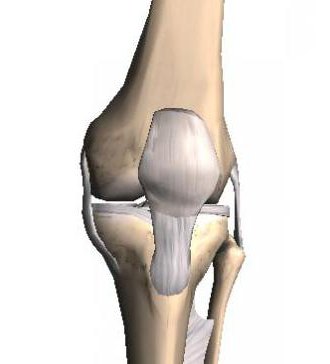

Строение коленного сустава

Коленный сустав соединяет в себе три кости: бедренную, большеберцовую и надколенник, укрывающий сустав спереди. Соединяющиеся площадки бедренной и большеберцовой костей неровные, поэтому между ними находится плотный гиалиновый хрящ для амортизации нагрузки (мениск). Костные поверхности внутри сустава тоже покрыты хрящем. Все составляющие сустава удерживают связки: боковые медиальная и латеральная, крестообразные передняя и задняя. Снаружи все это покрыто очень прочной суставной капсулой. Внутренняя поверхность капсулы выстлана синовиальной оболочкой, которая густо кровоснабжена и образует синовиальную жидкость. Она питает все структуры сустава путем диффузии, так как в хрящах нет кровеносных сосудов. В состав его входят хондроциты (до 10%), и межклеточное вещество (матрикс), который состоит из коллагеновых волокон, протеогликанов (их образуют хондроциты) и воды (до 80%).Протеогликаны, представленные гликозамингликанами и хондроитин сульфатом, связывают воду и волокна.